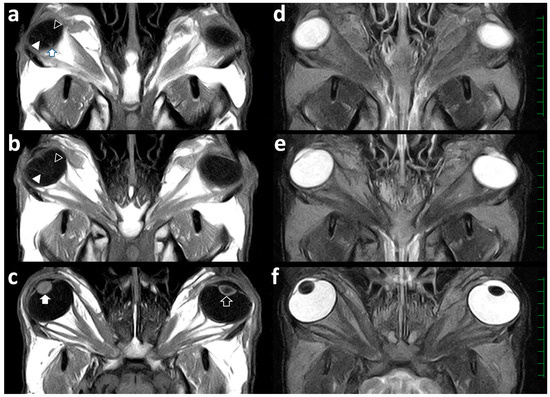

Figure 3.

Dorsal T1-weighted (a–c) and T2-weighted (d–f) views of the skull demonstrating the left and right eyeballs. (a) A V-shaped structure (empty and filled arrowheads) is seen within the vitreous body of the right eyeball. The tip of the V-shaped structure ends in the area of the optic nerve (arrow). (b) Two cystic structures are slightly evident in the center of one line of the V-shaped structure (empty arrowhead), despite no cystic structure being evident in another line (filled arrowhead) within the vitreous body of the right eyeball. A corn-like structure is not evident within the vitreous body of the left eyeball. (c) The right lens (filled arrow) is a spherical structure appearing entirely by a high signal intensity. The left lens (empty arrow) is normally visualized as a low signal intensity’s center surrounded by a high signal intensity’s line of the anterior and posterior lens structures. (d–f) Abnormal membranous structures are not evident within the vitreous bodies of the left and right eyeballs. The right lens is enlarged in the anteroposterior direction. Scale = 10 mm.

Intraocular structures such as the lens, the ciliary body, and the anterior chamber were not abnormal in the left eye. The dorsal sections of the right eye on the T1-weighted (Figure 3a,b) and FLAIR images revealed a V-shaped line within the vitreous body. The tip of the V-shaped structure was located at the beginning of the optic nerve. The medial line of the V-shaped structure was irregularly thickened at the center (Figure 3b). On the T1-weighted dorsal section of the right eye (Figure 3c), the lens appeared heterogeneously as a high signal intensity and was slightly thicker in the anteroposterior direction compared with that of the left eye. On the T1-weighted images, it was not possible to differentiate the border between the inner content of the lens and the anterior and posterior lens capsules. The lens in the right eye was heterogeneously seen as a low signal intensity on the T2-weighted (Figure 3f) and FLAIR images. There was no abnormality of the optic nerve, the extraocular muscles, or the fat tissues within the retrobulbar regions of both orbits. Additionally, there was no abnormality in the brain structures.

MRI has previously been applied to the skulls of two autopsied bovine cases, allowing the detection of bilateral microphthalmia and an abnormal shape of the globes in one case, and multiple formations of masses extending from the cavernous sinus resulting in injury of the cranial nerves in another case with cavernous sinus syndrome [5,24]. Recently, MRI could provide diagnostic evidence such as the defect of the lens structure within the extended eyeball, when examined for the anesthetized bovine case with anterior segment dysgenesis [4]. These previous results indicates that high quality images are helpful for identifying the pathological morphology of the affected eyeballs themselves, and evaluating their invasiveness toward and/or from the retrobulbar and skull’s structures, regardless of whether MRI is used antemortem or postmortem [4,5,24]. However, a discrepancy between the MRI and necropsy findings was also suggested when using MRI postmortem [5]. On the MRIs of both eyes in this case, the V-shaped structure of the detached retina and the cystic retinal lesions could barely be clarified within the right eyeball, but an atypical corn-like structure of the detached retina was not evident within the left eyeball. The low-field MRI scanner (0.3 Tesla) that was used for this case had limitations for visibility of the smaller structures compared with a high-field MRI scanner [23,25,28]. In this case, the cataractous lens appeared as a high signal intensity and a heterogeneous low signal intensity on the T1-weighted and T2-weighted images of the right eyeball, respectively. The MRIs of the right lens structure were recognizable from the normal signal intensities in the left lens structure but are unlikely to be similar to the signal intensities of the MRIs in human cases with cataracts [23]. The signal intensities of the cataractous lenses in the acquired types varied on T1-weighted images and were high on the T2-weighted images; this might have been attributable to the increased hydration [23]. On the other hand, there were no abnormalities in the signal intensities of T1-weighted and T2-weighted images of the congenital cataracts [23]. The different patterns of the signal intensities in the MRIs of cataracts may be associated with the differences in the internal substances accumulated within the cataractous lenses between human and bovine cases. Contrast MRIs can lead to different enhancements related to each ocular structure, facilitating the clear anatomical identification of the neighbor structures of the lens; this could be utilized for evaluating the cataracts [25]. Contrast MRIs can be useful for diagnosing bovine cataracts, if examined antemortem, because the effectiveness of this technique has already been confirmed for bovine cases [29]. Elevated diagnostic efficacies of MRIs for bovine ocular diseases are required by establishing age-matched or breed-matched indexes of bovine ocular structures such as basic MRI findings and normal measurement values [5].